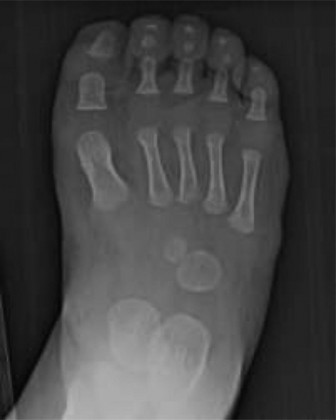

Pappas's classification, which includes eight grades based on the extent of fibular involvement and associated tibial bowing, also contributes to understanding the variability. Regardless of the classification used, the hallmark features include progressive LLD, anterior-medial bowing of the tibia, ankle valgus with or without a tarsal coalition, and absence or hypoplasia of the lateral rays of the foot (commonly the 4th and 5th toes, or even more profound lateral ray deficiencies). The fundamental challenge lies in restoring functional limb length, mechanical alignment, and a plantigrade, stable foot for ambulation.

Absence of Lateral Rays:

This is a hallmark feature, ranging from hypoplasia or absence of the 4th and 5th toes (often referred to as 'lateral ray deficiency') to a more extensive oligodactyly involving additional rays.

Pappas's classification, which delineates eight grades based on the extent of fibular involvement and associated tibial bowing, also provides valuable insights into the variability of this condition. Key pathological features universally observed include progressive LLD, anterior-medial bowing of the tibia, ankle valgus (often with talar hypoplasia or dysplasia), and hypoplasia or agenesis of the lateral rays of the foot, frequently involving the 4th and 5th toes, or more extensive oligodactyly. The overarching therapeutic challenge lies in restoring functional limb length, achieving mechanical alignment, and ensuring a plantigrade, stable foot for independent ambulation.

Lateral Ray Deficiency:

This is a hallmark feature, encompassing hypoplasia, aplasia, or absence of the lateral-most rays, most commonly the 4th and 5th toes. More extensive oligodactyly involving additional rays can also occur. This directly impacts foot width and stability.